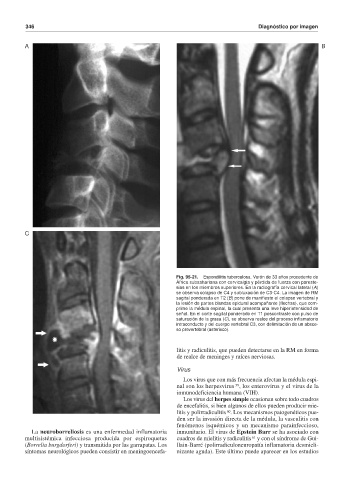

Fig. 95-21. Espondilitis tuberculosa. Varón de 33 años procedente de

África subsahariana con cervicalgia y pérdida de fuerza con pareste-

sias en los miembros superiores. En la radiografía cervical lateral (A)

se observa colapso de C4 y subluxación de C3-C4. La imagen de RM

sagital ponderada en T2 (B) pone de manifiesto el colapso vertebral y

la lesión de partes blandas epidural acompañante (flechas), que com-

prime la médula espinal, la cual presenta una leve hiperintensidad de

señal. En el corte sagital ponderado en T1 poscontraste con pulso de

saturación de la grasa (C), se observa realce del proceso inflamatorio

intraconducto y del cuerpo vertebral C3, con delimitación de un absce-

so prevertebral (asterisco).